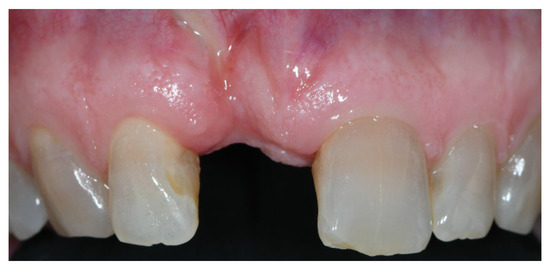

2.2. Clinical Procedures